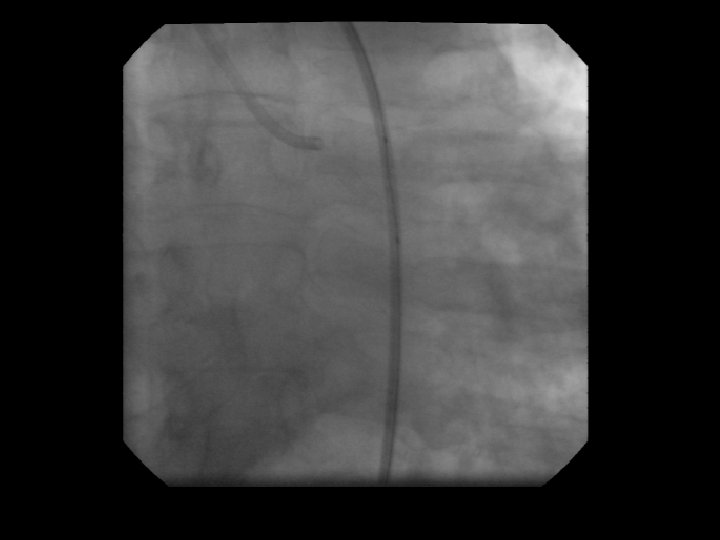

Stent Deployment

Stent Deployment • Correct size. • Correct Position. • Complete apposition Before Placing DES be sure no impending surgery